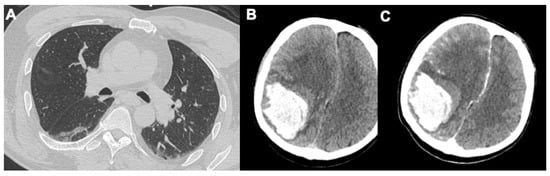

2.3. Pulmonary Embolism

3.1. Neurological Findings